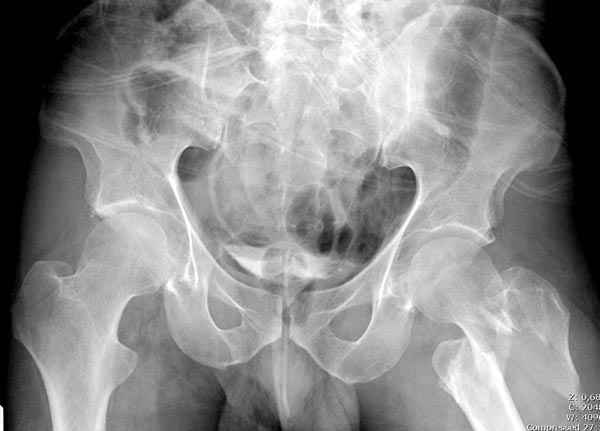

Предугадать распространение линий перелома при чрезвертельных и оскольчатых переломах трудно, поэтому для принятия правильного решения рекомендуется Компьютерно Томографические исследование.

При отсутствии КТ, снимок на вытяжении поможет увидеть общую картину расположения отломков, особенно потенциальные места введения импланта. Риск раскола в этом случае огромный, поэтому больной должен быть дообследован.

А так для лечения оскольчатых переломов подходят все методы, включая интра- и экстрамедуллярные в зависимости от опыта и наличия импланта.

Здесь пара похожих случаев.